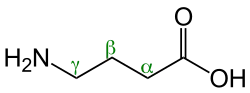

Gamma-aminobutyric acid (GABA) has an inhibitory effect on brain and spinal cord activity.[17] GABA is an amino acid that is the primary inhibitory neurotransmitter for the central nervous system (CNS). It reduces neuronal excitability by inhibiting nerve transmission. GABA has a multitude of different functions during development and influences the migration, proliferation, and proper morphological development of neurons. It also influences the timing of critical periods and potentially primes the earliest neuronal networks. There are two main types of GABA receptors: GABAa and GABAb. GABAa receptors inhibit neurotransmitter release and/or neuronal excitability and are a ligand-gated chloride channel. GABAb receptors are slower to react due to a GCPR that acts to inhibit neurons. GABA can be the culprit for many disorders ranging from schizophrenia to major depressive disorder because of its inhibitory characteristics being dampened.[25][26][27]